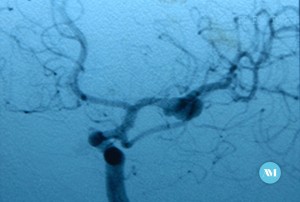

Un aneurisma es un ensanchamiento o abombamiento anormal de una parte de una arteria debido a debilidad en la pared del vaso sanguíneo.

- El cerebro (aneurisma cerebral)

Los aneurismas dentro del cuerpo y el cerebro a menudo no presentan síntomas. Los aneurismas del cerebro pueden expandirse sin reventar (ruptura). El aneurisma expandido puede presionar nervios y provocar visión doble, vértigos o dolores de cabeza. Algunos aneurismas pueden ocasionar tinnitus.

La cirugía puede implicar una incisión quirúrgica (abierta) con el colocado de un clip que elimina el aneurima, es una técnica de microcirugía y tiene una basta experiencia desde 1970. Sin embargo, algunos pacientes pueden someterse a una embolizaciónendovascular. Se pueden insertar espirales de metal a un aneurisma cerebral para hacer que el aneurisma coagule y reducir el riesgo de ruptura.